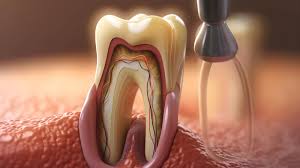

3.2 Profesyonel periodontal tedavi

- Diş taşlarının ve plakların düzenli olarak temizlenmesi (scaling ve root planing).

- İlerleyen vakalarda periodontal cerrahi, dişeti greftleri ve flep operasyonları uygulanabilir.

3.5 Rekonstrüktif cerrahi

- Serbest gingival greft veya bağ dokusu greftleri ile dişeti kalınlığı artırılır.

- Açığa çıkan diş kökü kapatılarak hem estetik hem fonksiyonel iyileşme sağlanır.